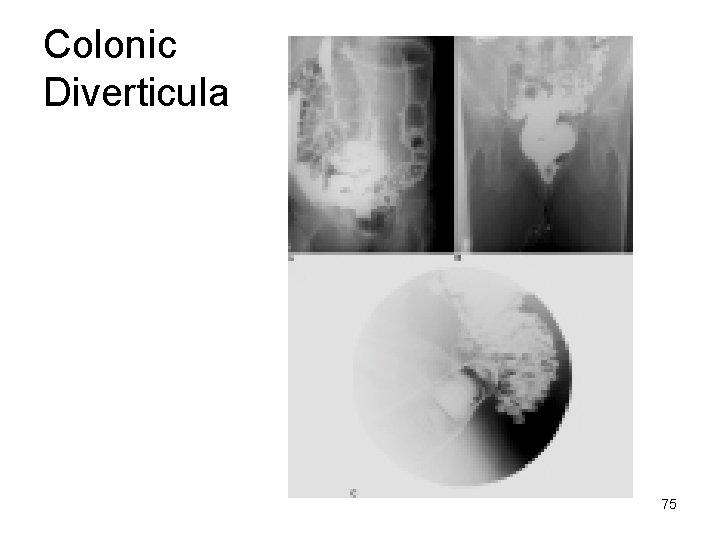

Colonic Diverticula Appear as round – oval Outpouchings of BA projecting beyond bowel lumen Vary in size 2 cm or more Tend to occur in clusters 74

Colonic Diverticula 75

1. The presence of diverticula _____inflammation Colonic Diverticula 2. Diverticula are associated with hypertrophy of the muscular layer of the bowel 3. Most common in _______ (95%) 4. Most patients are asymptomatic 76